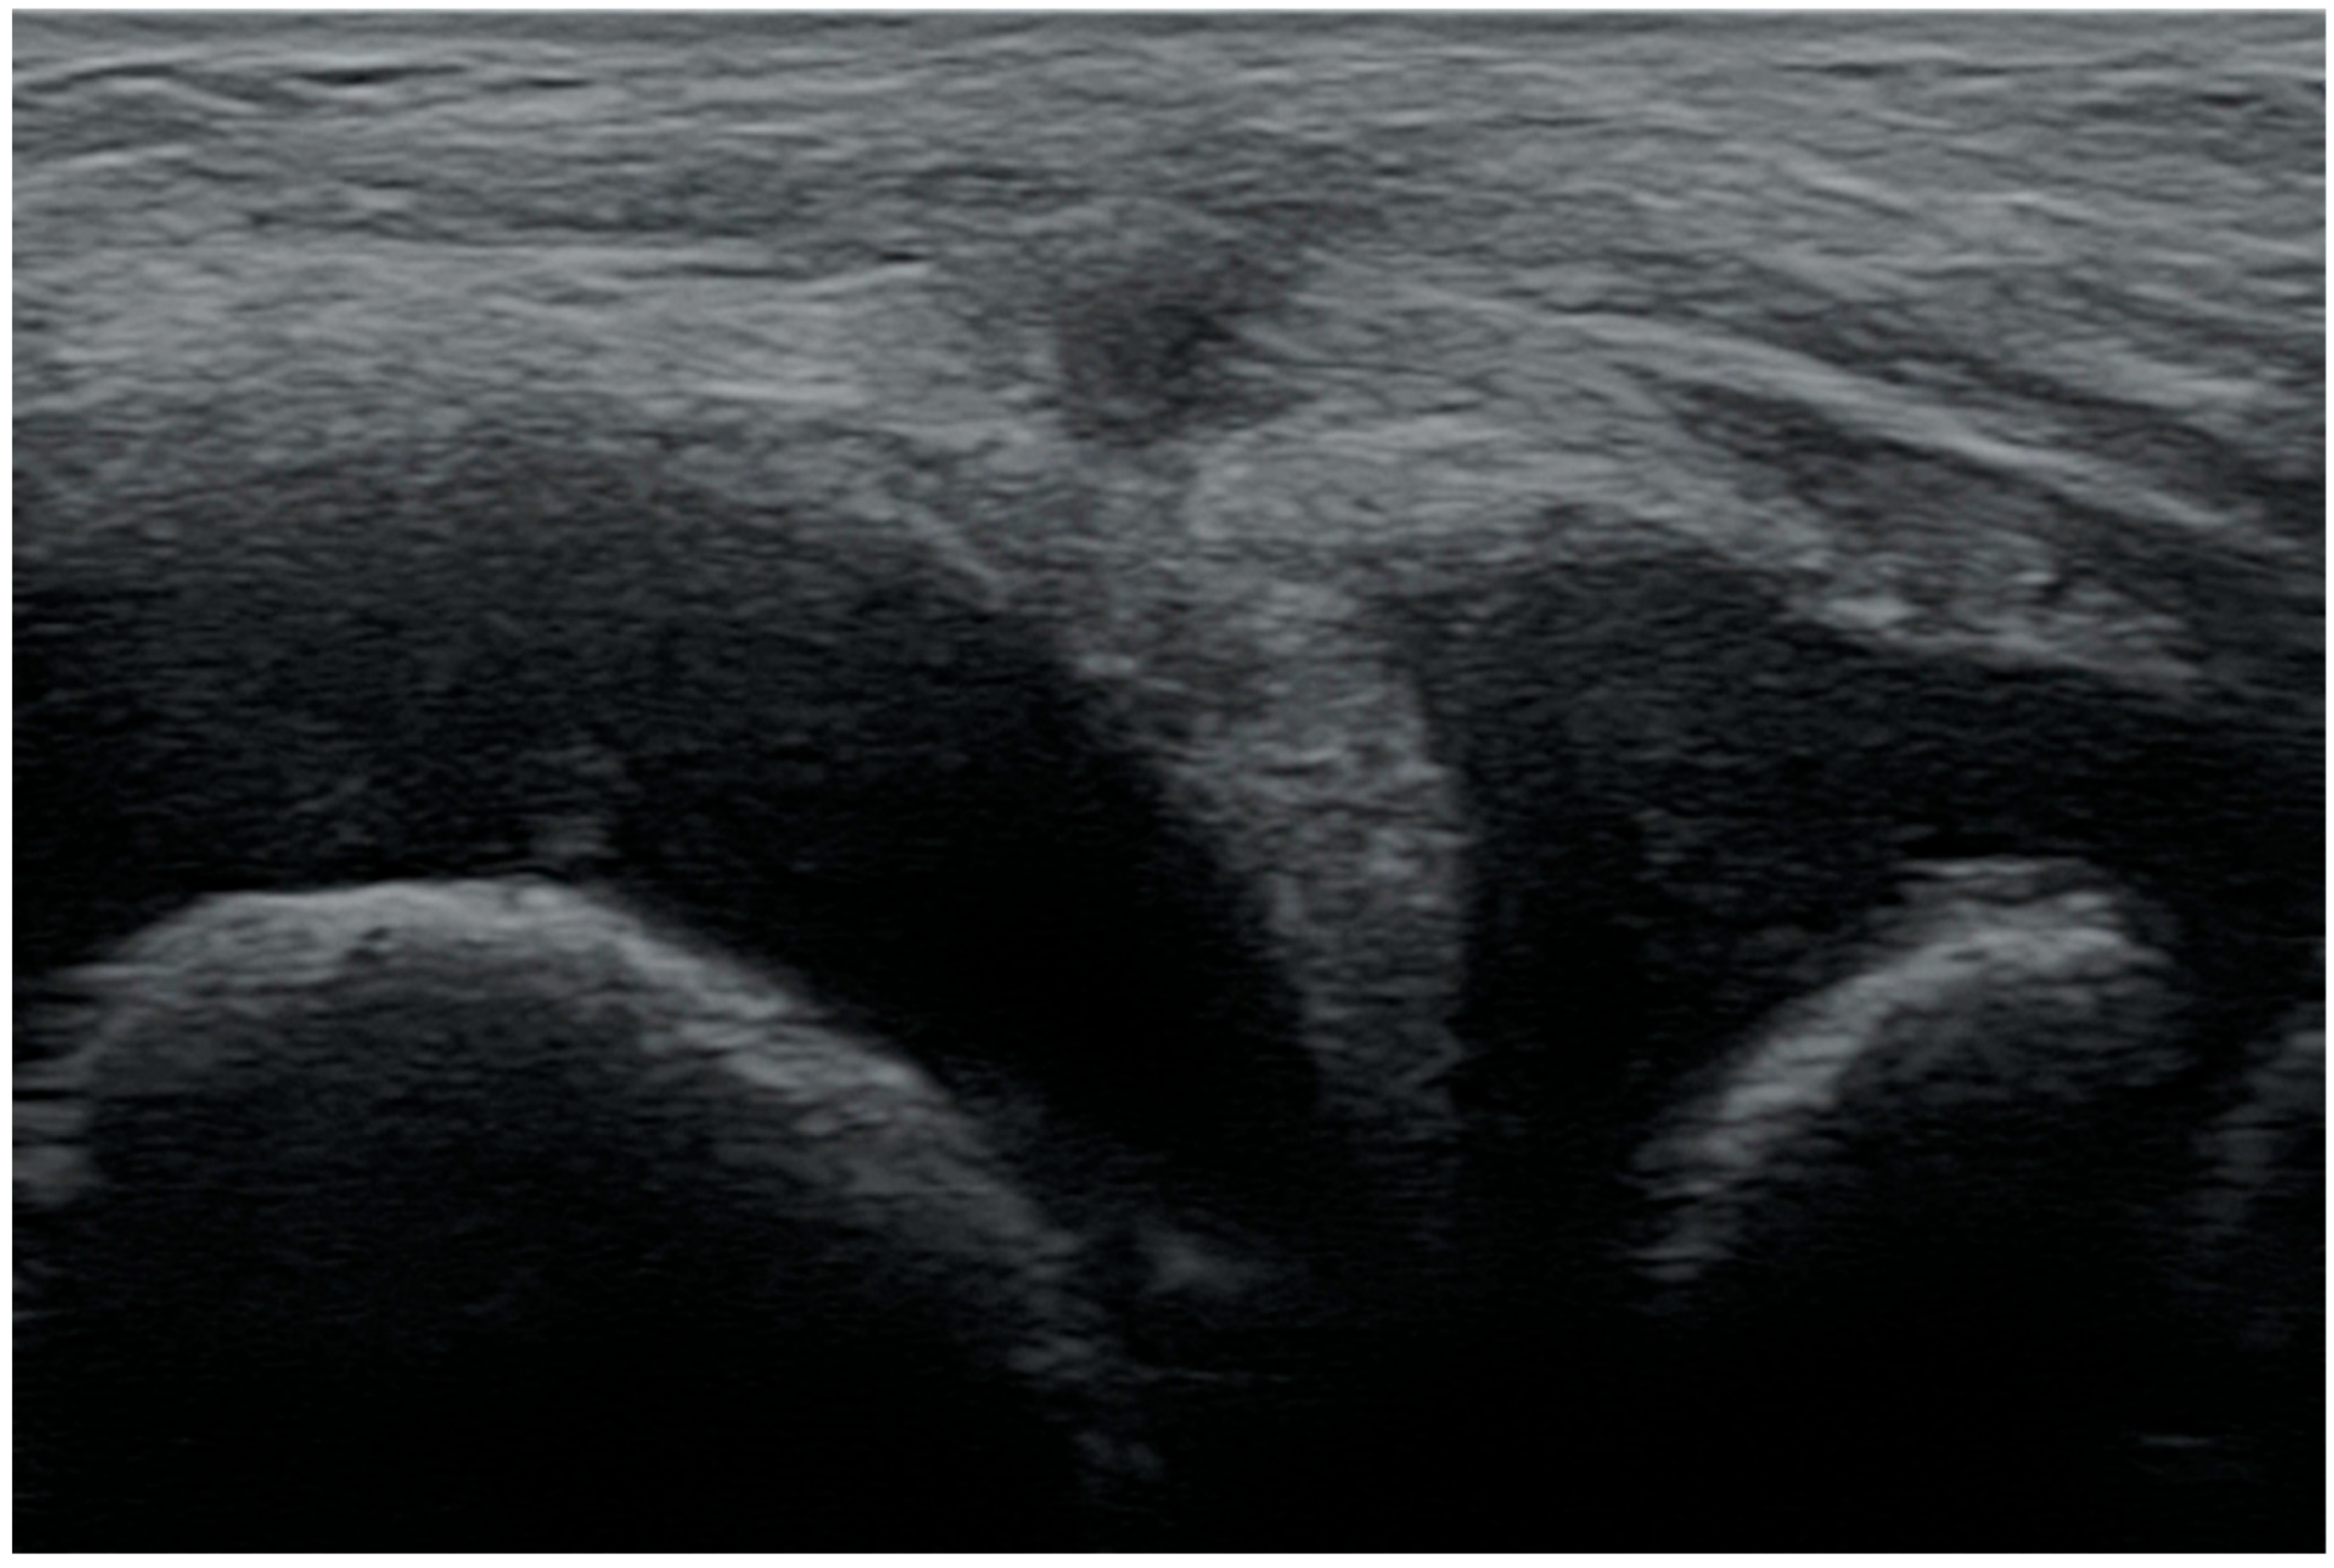

3.1.5. Degenerative Changes of Menisci

3.2. The Results of the Retrospective Analysis